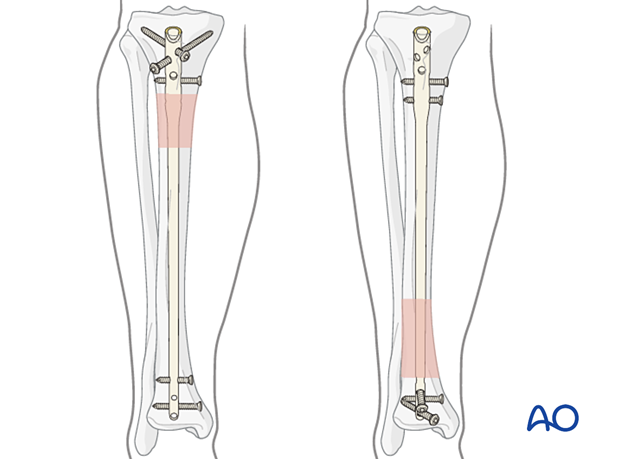

The diameter of the tibial medullary canal varies between 13 mm and 8 mm or less. Reamers can be used to enlarge the medullary canal for larger diameter nails. Such nails permit larger diameter locking screws. The strength and durability of screws and nails increases with their diameter. The medullary canal should be reamed so that it is slightly larger than the intended nail diameter (usually about 1.5 mm more), to ease nail insertion. The image illustrates a non-reamed nail on the left, and a reamed nail on the right. Stability is increased with the reamed technique, because the nail fits snugly in a longer portion of the tibial shaft.

Reaming is currently favored for most tibial nailing, but this should be done carefully when the isthmus of the tibial canal is narrow.

Non-reamed nailing was initially developed to theoretically reduce the risks of infection and pulmonary dysfunction from embolized medullary debris. These benefits have not been shown to be clinically significant. Since smaller diameter, “non-reamed” nails are mechanically weaker, particularly with regard to smaller locking screws, their reoperation rate is higher.

Such nails may be used for smaller diameter medullary canals, or selected indications, (eg, increased risk of infection) according to the surgeon’s preference. These nails are also ideally suited for use in healthcare settings where resources are limited, ie, lack of a fluoroscopy unit.